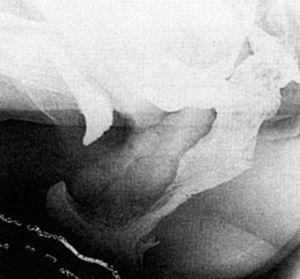

Proctografía de evacuación

Se diagnosticaron rectoceles y enteroceles aislados o bien la asociación de ambos, así como el grado o tamaño de éstos según la International Continence Society12 (fig. 1). De igual forma se valoró la posibilidad de prolapso oculto de recto o intususcepción rectal y contractura paradójica del músculo puborrectal.

Fig. 1. Defecografía con contraste intestinal. Rectocele y enterocele con asas intestinales.